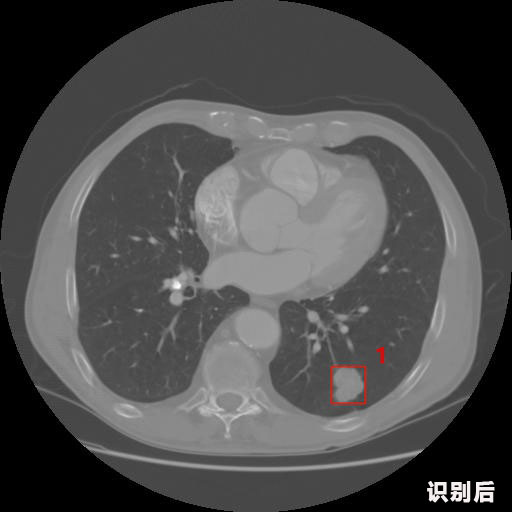

報告:

1.發(fā)現(xiàn)肺結(jié)節(jié)的可能性為95.56%---位于框指數(shù)位置:[331.70554 366.13406 365.21707 403.96234]